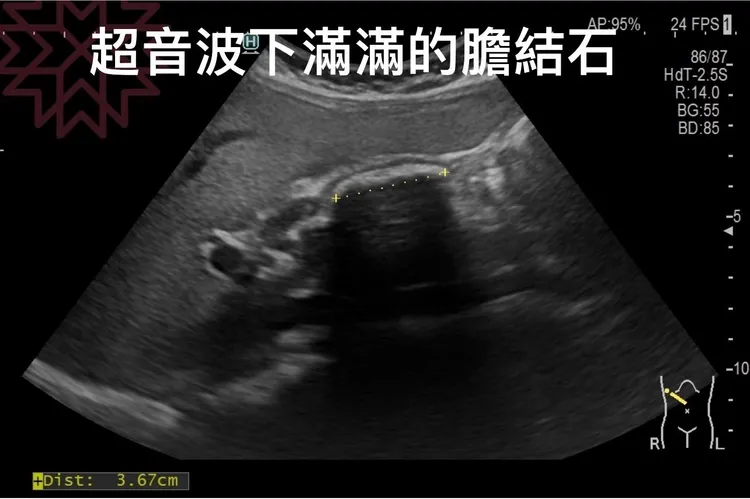

林相宏表示,患者發作時,尿液變深褐色,於是安排胃鏡、大腸鏡、超音波、內視鏡超音波等,徹底檢查胃、腸、胰臟、膽囊問題,發現胃鏡、大腸鏡都非常正常,反倒是膽囊裡面有夠恐怖,滿滿的結石,膽壁還增厚,建議手術處理。

不過這個病人超可愛,住院時竟把石頭一顆顆倒出來數,「結果竟然有 314顆結石,我的天啊!」患者在手術後,胃痛、脹氣、肚子痛也不再發生了。